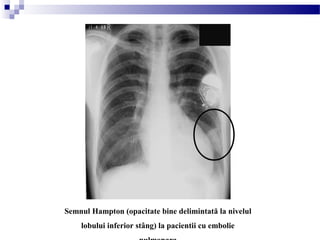

- semnul Hampton (opacitate rotunda).

Semnul Hampton (opacitate bine delimintată la nivelul

lobului inferior stâng) la pacientii cu embolie